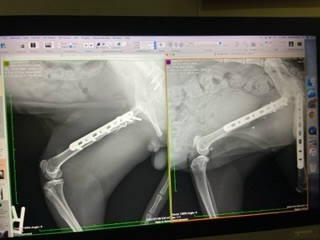

病院にてレントゲン撮影

※文末にレントゲン写真を2枚掲載しています。苦手な方は避けてください。

7/8 病院でハルくんのレントゲンを撮影してきました。

1ヶ月半ぶりの撮影ですが、無事に骨が固定されて、両脚の筋肉も大きく発達していました。獣医さんにも「制限なく走り回って大丈夫ですよ」と言われました。

念の為、半年後にプレートのズレがないか確認しますが、ひと安心です。両脚骨折で這う事しかできなかったハルくんがここまで回復できてびっくりです。良かった!

※レントゲン写真

(左が7月撮影:筋肉が盛り上がり、プレートが骨と筋肉によりしっかり固定されている折れた骨も治っている)